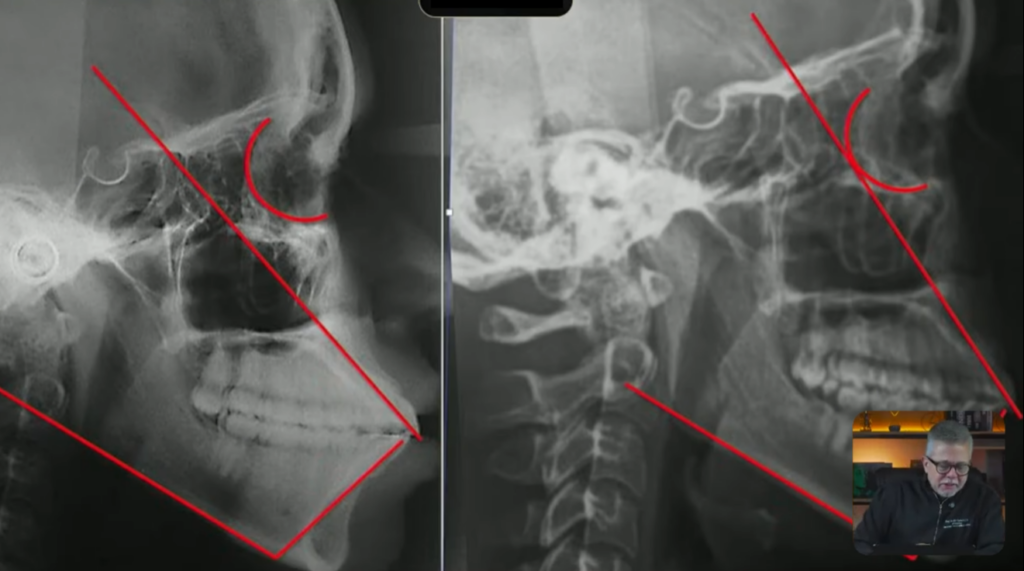

Quando eu vou fazer o tratamento dessa classe 2, eles estão em uma posição ideal, eles estão bem posicionados, o superior ele está quase tangenciando a órbita, o incisivo superior está levemente lingualizado:

Esse inferior está quase bem posicionado,

só que deu para observar que tanto o superior quanto o inferior, o superior está levemente lingualizado e o inferior está levemente vestibularizado:

Se vocês observarem, aqui o longo eixo do incisivo, aqui o longo eixo do incisivo agora está tangenciando a órbita, e aqui o longo eixo do incisivo inferior está mais ou menos com 90 graus com a base da mandíbula: